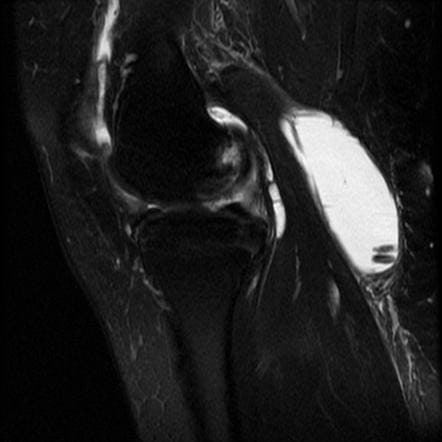

УЗИ - самый доступный и безопасный метод, саму кисту прекрасно видно.

МРТ, когда нужно заглянуть дальше, например, чтобы исключить повреждение заднего рога мениска или крестообразных связок - такие глубоко залегающие структуры по УЗИ не видно.

Иногда в полости кисты можно найти какие-нибудь образования, которые мигрировали из полости сустава (кальцинаты, костные тела, хрящевые тела, костно-хрящевые).